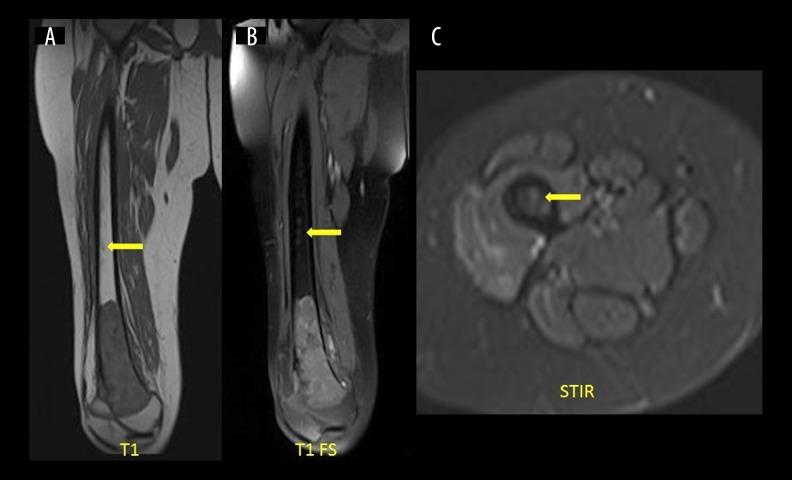

It is imperative that bone tumour margin and extent of tumour involvement are accurately assessed pre-operatively in order for the surgeon to attain a safe surgical margin. In this study, we comprehensively assessed each of the findings that influence surgical planning, on various MRI sequences and compared them with the gold standard - pathology.

MATERIAL/METHODS: In this prospective study including 21 patients with extremity bone tumours, margins as seen on various MRI sequences (T1, T2, STIR, DWI, post-gadolinium T1 FS) were measured and biopsies were obtained from each of these sites during the surgical resection. The resected tumour specimen and individual biopsy samples were studied to assess the true tumour margin. Margins on each of the MRI sequences were then compared with the gold standard - pathology. In addition to the intramedullary tumour margin, we also assessed the extent of soft tissue component, neurovascular bundle involvement, epiphyseal and joint involvement, and the presence or absence of skip lesions.

T1-weighted imaging was the best sequence to measure tumour margin without resulting in clinically significant underestimation or overestimation of the tumour extent (mean difference of 0.8 mm; 95% confidence interval between -0.9 mm to 2.5 mm; inter-class correlation coefficient of 0.998). STIR and T1 FS post-gadolinium imaging grossly overestimated tumour extent by an average of 16.7 mm and 16.8 mm, respectively (P values <0.05). Post-gadolinium imaging was better to assess joint involvement while T1 and STIR were the best to assess epiphyseal involvement.

T1-weighted imaging was the best sequence to assess longitudinal intramedullary tumour extent. We suggest that osteotomy plane 1.5 cm beyond the T1 tumour margin is safe and also limits unwarranted surgical bone loss. However, this needs to be prospectively proven with a larger sample size.

为使外科医生获得安全的手术切缘,术前准确评估骨肿瘤的边界和肿瘤累及范围至关重要。在本研究中,我们全面评估了各种MRI序列上影响手术规划的各项发现,并将其与金标准——病理结果进行比较。

材料/方法:在这项前瞻性研究中,纳入了21例四肢骨肿瘤患者,测量了各种MRI序列(T1、T2、短TI反转恢复序列(STIR)、扩散加权成像(DWI)、钆增强T1脂肪抑制序列(T1 FS))上所见的边界,并在手术切除过程中从每个部位获取活检样本。对切除的肿瘤标本和各个活检样本进行研究,以评估真正的肿瘤边界。然后将每个MRI序列上的边界与金标准——病理结果进行比较。除了评估髓内肿瘤边界外,我们还评估了软组织成分的范围、神经血管束受累情况、骨骺和关节受累情况以及跳跃性病变的有无。

T1加权成像在测量肿瘤边界方面是最佳序列,不会导致对肿瘤范围的临床显著低估或高估(平均差异为0.8mm;95%置信区间为-0.9mm至2.5mm;组内相关系数为0.998)。钆增强后的STIR和T1 FS成像分别平均高估肿瘤范围16.7mm和16.8mm(P值<0.05)。钆增强成像在评估关节受累方面更佳,而T1和STIR在评估骨骺受累方面最佳。

T1加权成像在评估纵向髓内肿瘤范围方面是最佳序列。我们建议在T1肿瘤边界以外1.5cm处进行截骨是安全的,并且还能限制不必要的手术骨质丢失。然而,这需要通过更大样本量的前瞻性研究来证实。